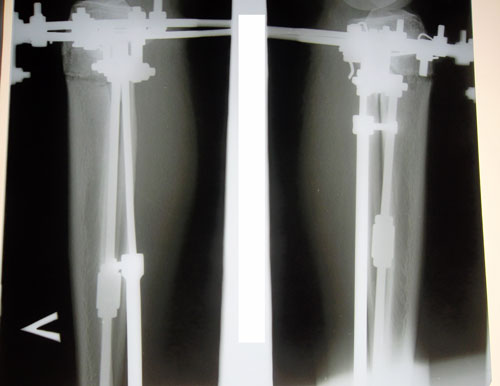

В процессе исправления деформации ног, штрихи!

Рентген в 2 месяца.

Сращение отличное, снимать можно в первых числах апреля, но Н.Н. будет отсутствовать с 1 - 14 апреля. По этому, рекомендую приехать на снятие аппаратов 15 апреля (так будет лучше).